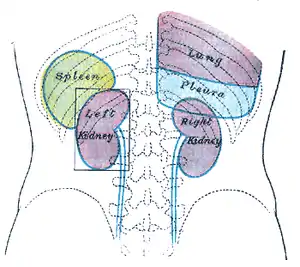

The spleen is underneath the left part of the diaphragm, and has a smooth, convex surface that faces the diaphragm. It is underneath the ninth, tenth, and eleventh ribs. The other side of the spleen is divided by a ridge into two regions: an anterior gastric portion, and a posterior renal portion. The gastric surface is directed forward, upward, and toward the middle, is broad and concave, and is in contact with the posterior wall of the stomach. Below this it is in contact with the tail of the pancreas. The renal surface is directed medialward and downward. It is somewhat flattened, considerably narrower than the gastric surface, and is in relation with the upper part of the anterior surface of the left kidney and occasionally with the left adrenal gland.

An easy way to remember the anatomy of the spleen is the 1×3×5×7×9×10×11 rule. The spleen is 1 by 3 by 5 inches (3 by 8 by 13 cm), weighs approximately 7 oz (200 g), and lies between the 9th and 11th ribs on the left-hand side and along the axis of the 10th rib. The weight varies between 1 oz (28 g) and 8 oz (230 g) (standard reference range),[12] correlating mainly to height, body weight and degree of acute congestion but not to sex or age.[13]

Maximum length of spleen on abdominal ultrasonography Back of lumbar region, showing surface markings for kidneys, ureters, and spleen

Back of lumbar region, showing surface markings for kidneys, ureters, and spleen Side of thorax, showing surface markings for bones, lungs (purple), pleura (blue), and spleen (green)